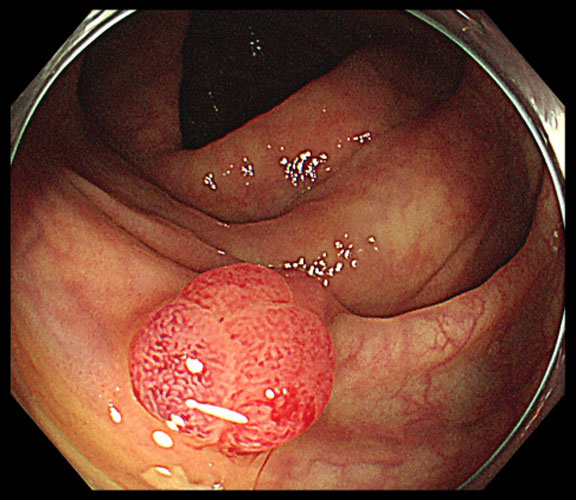

大腸ポリープ

大腸ポリープは大腸粘膜にできる良性の病変です。

放置するとがんの元になる腫瘍性のポリープである腺腫(せんしゅ)と、がん化しないその他のポリープがあります。

小さなポリープは特に症状は出ませんが、ポリープが大きくなると出血しやすくなり、血便の原因となることがあります。

大腸内視鏡検査による切除が有効であり、早期発見・早期切除することで大腸がんの予防につながります。

小さなポリープであれば日帰りでの内視鏡切除が可能ですが、大きなものでは入院が必要になりますので、早期の内視鏡治療がおすすめです。